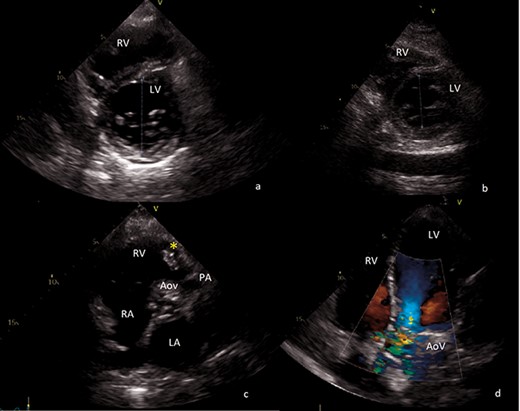

Both right and left ventricle grossly dilated due to excessive volume overload (end-diastolic left ventricle diameter of 68 mm) (Fig. 1a).

Severe PV insufficiency, with a single sizable vegetation of about 4 cm provoking right ventricular outflow obstruction (Fig. 1c)

Severe aortic valve regurgitation with multiple vegetations, the largest of about 11 mm length, protruding to the aorta as well as to the left ventricle outflow tract (Fig. 1d).

Before discharge, transthoracic echocardiogram revealed well-functioning bioprostheses, with prompt recovery of both right and left ventricles (Fig. 1b). Native valves’ culture was negative. Follow-up blood tests and echocardiogram at 6 and 12 months after surgery were free of recurrence.

Transthoracic echocardiography images. (a) Preoperative short axis view of left ventricle. End-diastolic left ventricle diameter of 68 mm. (b) Postoperative short axis view of left ventricle. End-diastolic left ventricle diameter of 43 mm. (c) Sizable vegetation (yellow asterisk) of about 4 cm provoking right ventricular outflow obstruction. (d) Four-chamber view, showing severe aortic regurgitation. AoV aortic valve; LA left atrium; LV left ventricle; PA pulmonary artery; RA right atrium; RV right ventricle.